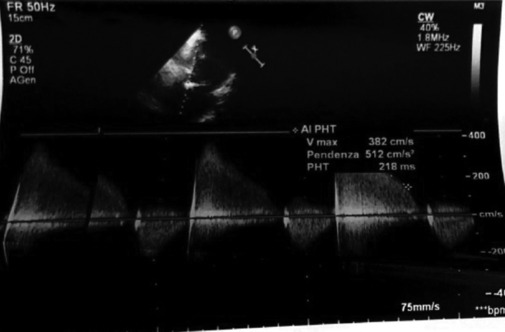

The pandemic changed the type of patients. The concept of "patient at the center" became concrete. The execution of simple consultancy was overcome to create effective collaboration and fruitful exchanges between specialists. The "Heart Team" model is on increasing affirmation. The TEAM-BASED approach in the cardiology field is successfully used in patients suffering from ischemic heart disease and valvulopathies for the choice of possible treatments. Degenerative type Sao is the most frequent valvulopathy among the valvulopathies in Western countries and its incidence is correlated with age. In high-risk patients, percutaneous valve replacement (transcatheter aortic valve implantation) is the most valid therapeutic option. The implantation of biological prostheses raises the problem of both degeneration and dysfunction of the prosthesis itself over time in subjects of advanced age and with comorbidities. In this scenario, valve-in-valve (VinV) is a valid therapeutic alternative in high-risk patients. A clinical case of aortic prosthetic degeneration, as an outcome of endocarditis, treated with VinV is presented. The therapeutic decision was made by an "Electronic Heart Team" which represents a further evolution of the treatment pathways and reduces the distance between the specialists in "Hub" Centers and the "Spoke" center.